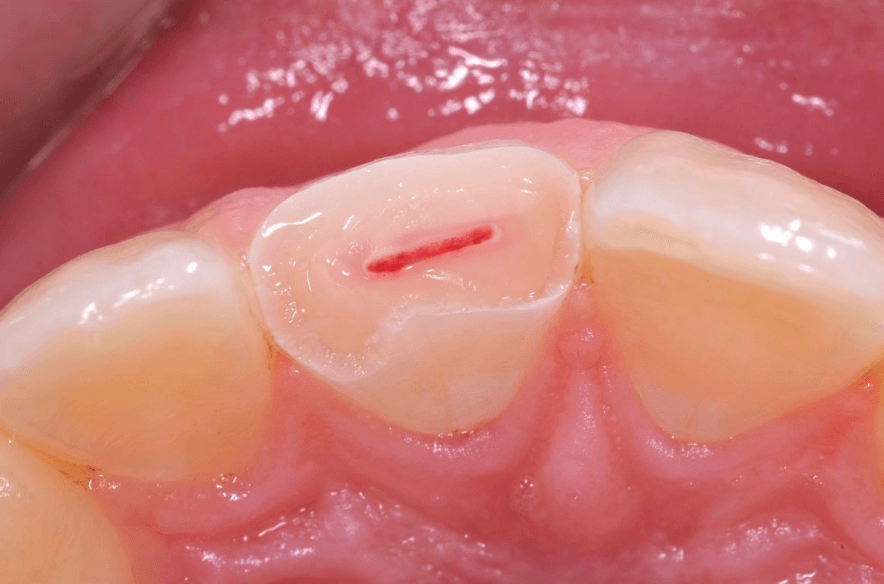

Pulp Capping

In some cases, healthy pulp may become exposed due to decay or trauma. If there are no signs of infection, a dentist may perform a pulp capping procedure to preserve the tooth.

There are two main types of pulp capping:

- Direct pulp capping is used when the pulp is fully exposed.

- Indirect pulp capping is performed when the pulp is not directly exposed but is very close to the surface. This technique helps protect the pulp and promotes natural dentin regeneration.